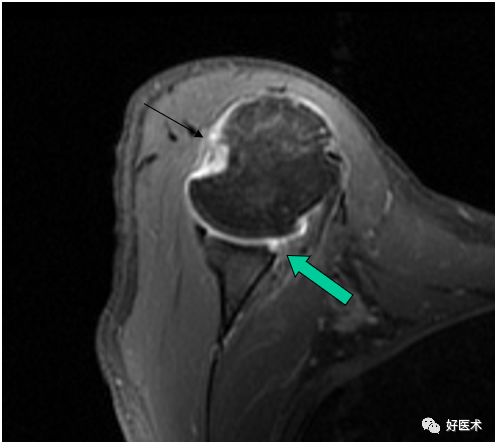

SLAP、Bankart合并Hill-Sach损伤

Hill-Sachs损伤

-

Hill-Sachs损伤:肩关节前脱位时,肱骨头撞向关节盂缘可导致肱骨头的后外侧的嵌插骨折

MR间接关节造影1.5T轴位T1W脂肪抑制

MR间接关节造影1.5T冠状面T1W脂肪抑制

Hill-sachs,Bankart,关节囊损伤